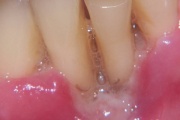

kaaries igemeäärel

kaaries